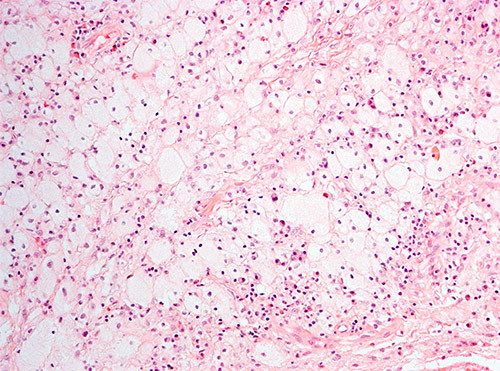

Histologisk undersøkelse hadde vist inflammatorisk prosess med mange makrofager, spredtliggende og enkelte grupper av lymfoide celler, spredte plasmaceller, nøytrofile og eosinofile granulocytter (fig 1). Atypiske celler, granulomatøs betennelse eller vaskulitt var ikke påvist. Spesialfarging for sopp, bakterier og mykobakterier var negativ. Ved rutinemessig immunhistokjemisk undersøkelse var makrofagene positive for CD68. De små lymfoide cellene var B-celler positive for CD20 samt T-celler positive for CD4 og CD8.

Ved ny gransking ble det poengtert at makrofagene hadde rikelig med lyst skummende cytoplasma, forenlig med skummakrofager. Immunfenotyping viste at de CD68-positive makrofagene var negative for CD1a og S100. Patolog konkluderte med at det morfologiske bildet passet med Erdheim-Chesters sykdom.

Ved immunhistokjemiske undersøkelser finner man ved Erdheim-Chesters sykdom CD68-positive og CD1a-negative histiocytter, mens man ved langerhanscellehistiocytose påviser CD1a-positive histiocytter. I de fleste tilfellene av Erdheim-Chesters sykdom (80  %) er farging for S100-protein negativ. Diagnosen Erdheim-Chesters sykdom settes ut fra en kombinasjon av kliniske, bildediagnostiske og histologiske funn.